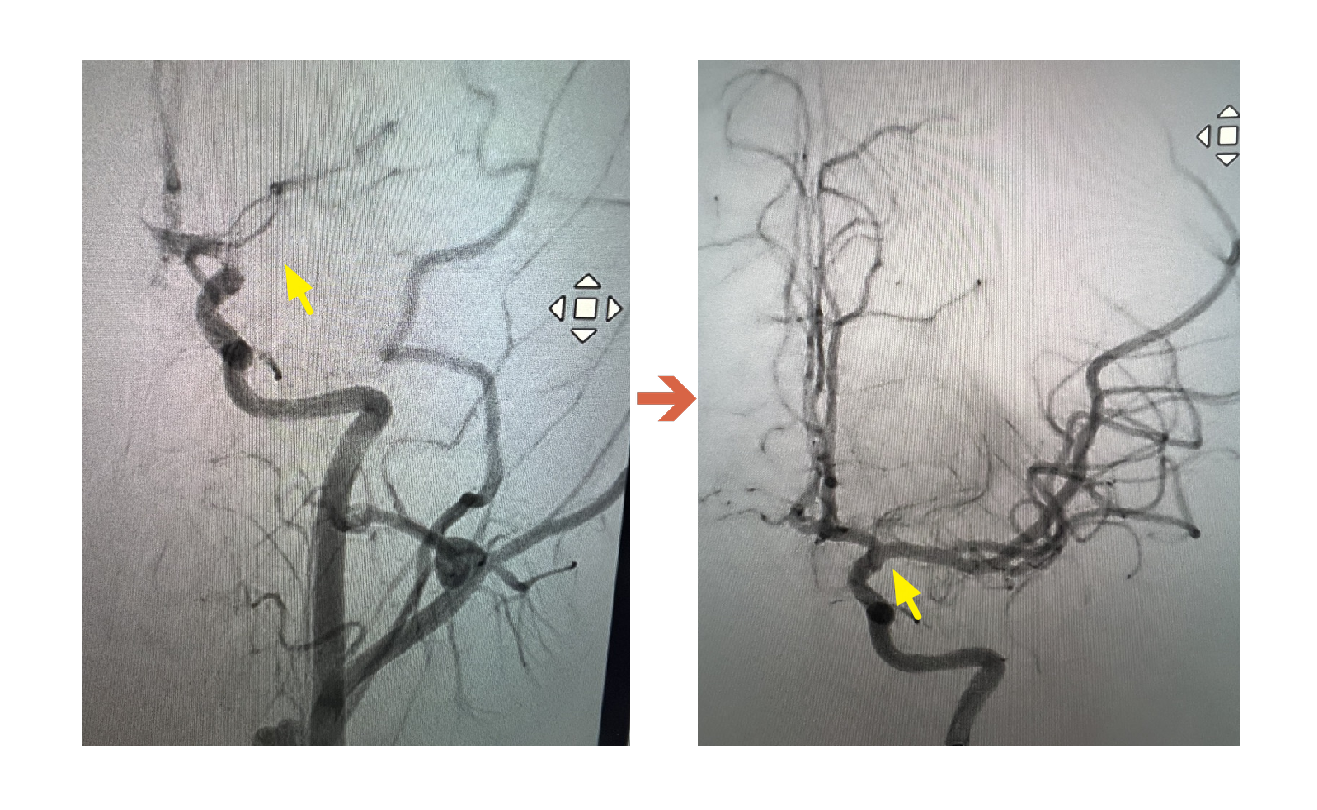

聯新國際醫院表示,該名學生被送往該院急診,影像檢查結果出爐後,神經內科醫師李振華迅速判讀,確定為左側中大腦動脈栓塞造成缺血性腦中風。在與家屬充分溝通後,影像醫學科主任暨取栓醫師郭葉璘隨即與取栓團隊進行急性腦中風顱內動脈血栓移除(Intra-arterial thrombectomy, IAT),並從腹股溝導引導管至左側中大腦動脈阻塞處,採用強力抽吸方式清除血栓。手術從開始到打通血管僅約10分鐘,成功取出4個血栓,最大達1.1公分。術後患者血流恢復暢通。

郭葉璘說明,左側大腦掌管語言中樞、身體右側活動能力及視覺與空間感知區域,中大腦動脈是負責供應大腦三分之二的重要血流。磁振造影中的擴散權重影像序列(DWI),能在中風發生後30分鐘內偵測腦部受損區域。檢查顯示該學生的左側中大腦動脈完全阻塞,磁振中的擴散權重影像序列也出現一塊淡淡的受損區域,這表示阻塞的危險性正快速提高中。若不即時處理,這片受損區域會持續擴大,腦部將因血栓壓迫而腫脹,同時往下壓迫腦幹,危及呼吸與心跳中樞,甚至造成生命危險。